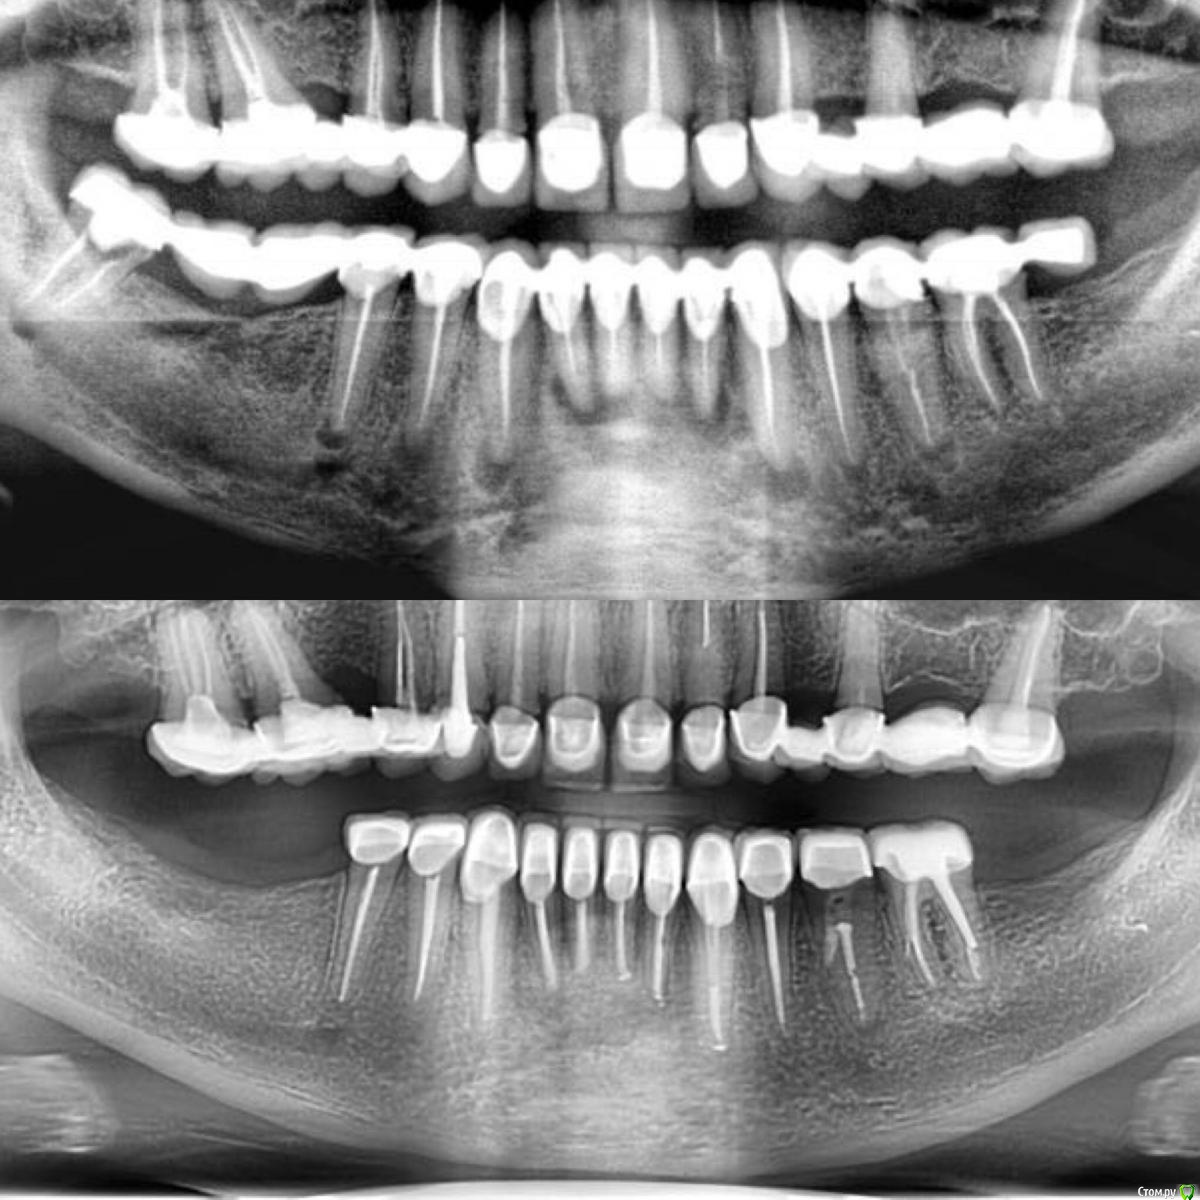

сирена Опубликовано 16 сентября, 2018 Поделиться Опубликовано 16 сентября, 2018 А что там с 35?Как то он не вписывается в общую красивую картину. Ссылка на комментарий

Kolchanov Опубликовано 16 сентября, 2018 Поделиться Опубликовано 16 сентября, 2018 (изменено) Ээээ, Наталья. Старая мудрая поговорка говорит, что: горбун не заметит твоих бородавок, если ты не заметишь его горба. Понятно, что там с 35. Все будет ОК. Изменено 16 сентября, 2018 пользователем Kolchanov Ссылка на комментарий

Гарриевич Опубликовано 17 сентября, 2018 Автор Поделиться Опубликовано 17 сентября, 2018 А что там с 35?Как то он не вписывается в общую красивую картину.В 3,5 я пробовал попытался убрать стекловолокно без скопа, в это 50/50 себе затея. В итоге сделал перфо. Потом отправил к себе же на скоп и убрал его за считанные минуты Ссылка на комментарий

сирена Опубликовано 17 сентября, 2018 Поделиться Опубликовано 17 сентября, 2018 Ээээ, Наталья. Старая мудрая поговорка говорит, что: горбун не заметит твоих бородавок, если ты не заметишь его горба. Вы,часом,не Конфуций? В 3,5 я пробовал попытался убрать стекловолокно без скопа, в это 50/50 себе затея. В итоге сделал перфо. Потом отправил к себе же на скоп и убрал его за считанные минутыДа я не за перфу,с этим ,и правда,всё понятно.Просто на всех зубах полная редукция очага,а на этом ещё нет.А времени сколько прошло?От лечения? Ссылка на комментарий

Гарриевич Опубликовано 18 сентября, 2018 Автор Поделиться Опубликовано 18 сентября, 2018 Вы,часом,не Конфуций? Да я не за перфу,с этим ,и правда,всё понятно.Просто на всех зубах полная редукция очага,а на этом ещё нет.А времени сколько прошло?От лечения? он закрывался самый последний. Прошло около полугода по моему, может. Кто больше, может сильно больше) Ссылка на комментарий

DmitrySH Опубликовано 19 сентября, 2018 Поделиться Опубликовано 19 сентября, 2018 Юра, действительно все круто! А с верхом что? Не бывает же, что изначально внизу было все плохо, а верх хорошо. Ссылка на комментарий

Гарриевич Опубликовано 2 октября, 2018 Автор Поделиться Опубликовано 2 октября, 2018 Юра, действительно все круто! А с верхом что? Не бывает же, что изначально внизу было все плохо, а верх хорошо. Спасибо, Дим)с верхом тоже все плохо, пациент пока все собирается с духом и прочими расходами Ссылка на комментарий